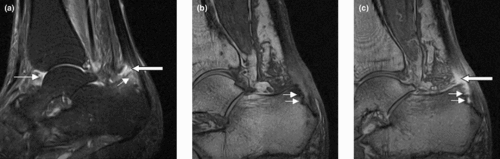

Enthesitis is inflammation of the entheses, the sites where tendons or ligaments insert into the bone.[1][2] It is also called enthesopathy, or any pathologic condition involving the entheses. The entheses are any point of attachment of skeletal muscles to the bone, where recurring stress or inflammatory autoimmune disease can cause inflammation or occasionally fibrosis and calcification. One of the primary entheses involved in inflammatory autoimmune disease is at the heel, particularly the Achilles tendon.

It is associated with HLA B27 arthropathies like ankylosing spondylitis, psoriatic arthritis, and reactive arthritis.[3][4] Symptoms include multiple points of tenderness at the heel, tibial tuberosity, iliac crest, and other tendon insertion sites.